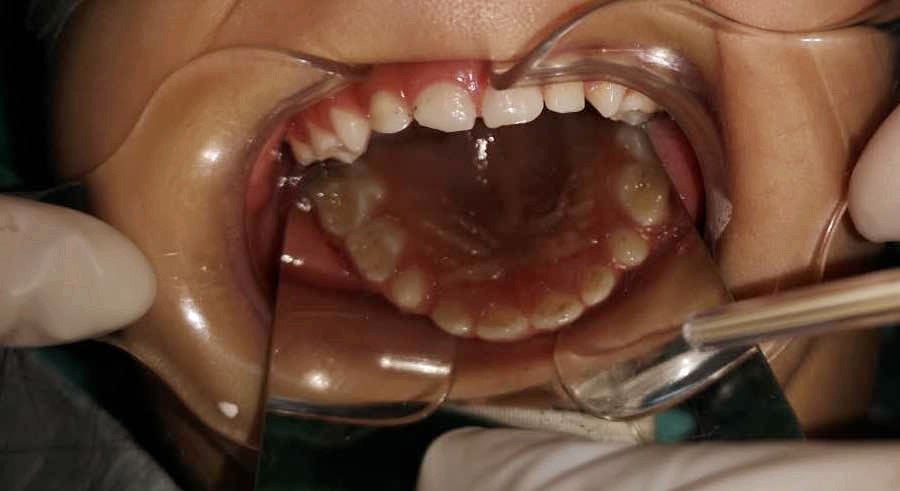

丁彬醫(yī)師和申家麗醫(yī)師正在為小患者進行全麻下牙齒調(diào)節(jié)

兩個多小時后,這一多達8顆患牙的復(fù)雜調(diào)節(jié)順利完成。在這期間,鑫鑫的心率和血壓一直被密切監(jiān)測著,一切都很正常。